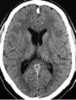

Unilateral obstruction of foramen of Monro

Asymmetrically enlarged lateral ventricles